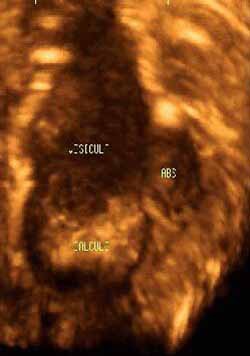

Cholecystitis with perivesicular abscess

Over the course of a week, a 69-year-old man with a history of gallstones had developed a fever of unknown origin and pain in the right hypochondrion.

An ultrasound study of the abdomen revealed a distended gallbladder containing microlithiasis, bile-plug syndrome, poorly defined internal walls containing a thick liquid material, and a poorly defined border with the adjacent liver bed.

The patient underwent emergency surgery, which confirmed the diagnosis of perforated cholecystitis with perivesicular abscess.

![]() |

| Figure 3. Volumetric reconstruction of the gallbladder obtained with a surface-rendering technique clearly depicts the distended gallbladder with microlithiasis, bile-plug syndrome, poorly defined internal walls containing a thick liquid material, and a poorly defined border with the adjacent liver bed. |